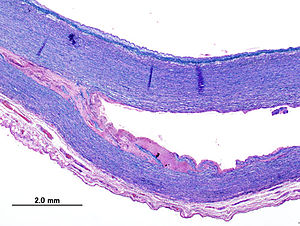

The diameter of the aorta decreases in size from its thoracic portion to the abdominal and infrarenal portions. A normal aorta shows a reduction in medial elastin layers from the thoracic area to the abdominal portion. Elastin and collagen content are also reduced. AAAs develop following degeneration of the media. The degeneration ultimately may lead to widening of the vessel lumen and loss of structural integrity.

A multidisciplinary research program supported by the US National Heart, Lung, and Blood Institute identified proteolytic degradation of aortic wall connective tissue, inflammation and immune responses, biomechanical wall stress, and molecular genetics as mechanisms important in the development of AAA. Similarly, surgical specimens of AAA reveal inflammation, with infiltration by lymphocytes and macrophages; thinning of the media; and marked loss of elastin.

Through gene microarray analysis, various genes involved in extracellular matrix degradation, inflammation, and other processes observed in AAA formation have been shown to be up-regulated, while others that may serve to prevent this occurrence are down-regulated. The combination of proteolytic degradation of aortic wall connective tissue, inflammation and immune responses, biomechanical wall stress, and molecular genetics represents a dynamic process that leads to aneurysmal deterioration of aortic tissue.